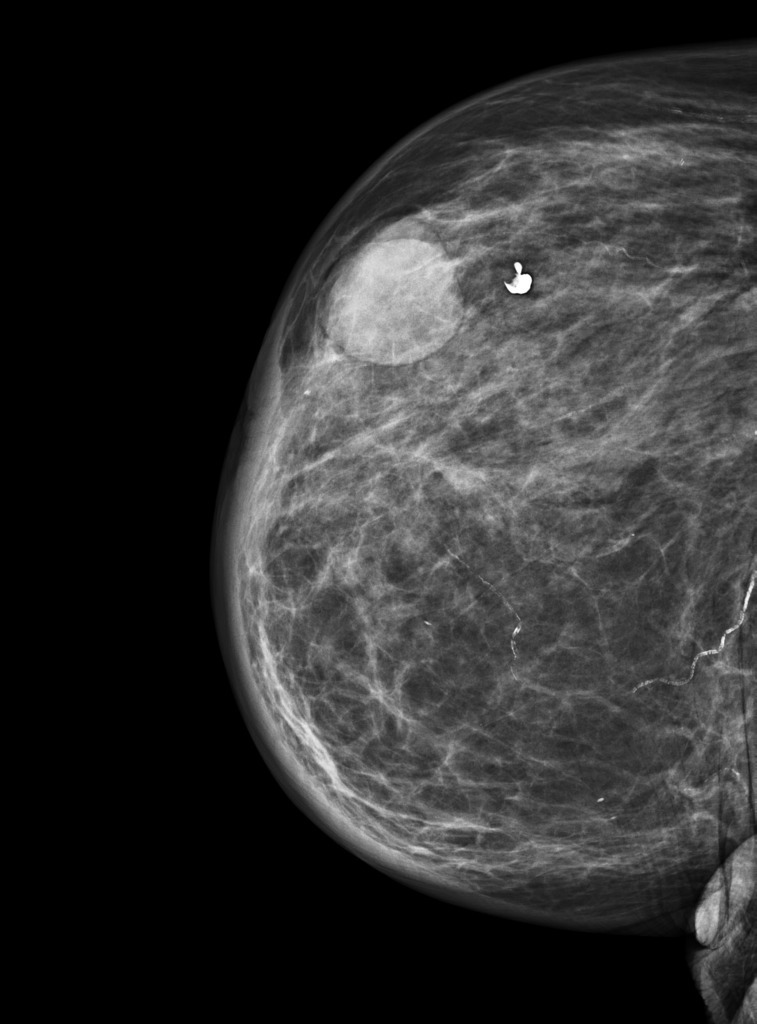

What is a breast cyst and how do they present?

How would you diagnose and manage a breast cyst?

What complications can happen from breast cysts?